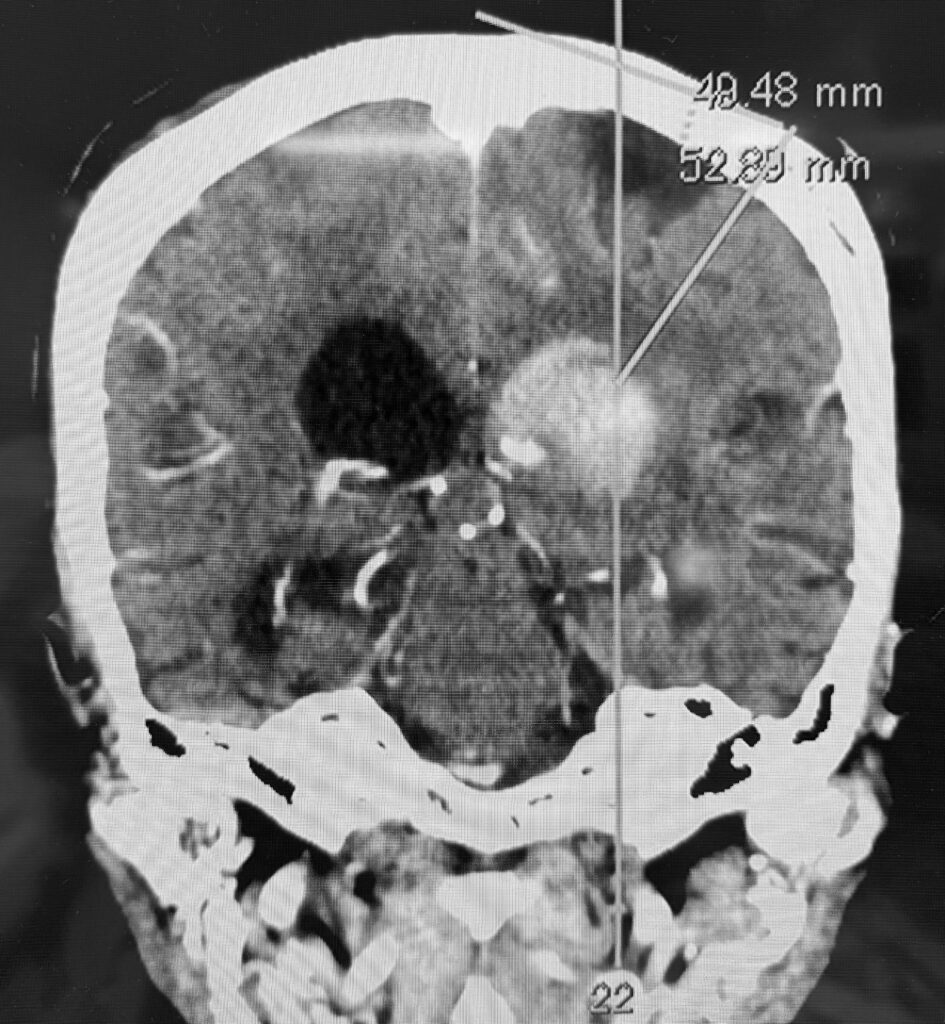

視床出血、脳室穿破の症例で、患者さんはご高齢なので内視鏡で低侵襲に血腫除去したいという要望でした。ご要望にお応えし、局所麻酔で3センチ切開し、1センチの穴を開けて血腫除去してきました。無事に血腫は取れたので今頃はリハビリテーションに励んでいることでしょう。

私は上記の写真のように個別にアプローチを決定し、透明シースを挿入し、内視鏡下に血腫除去する方法で良好な結果を得ています。ただし、エビデンスとなるとある程度の症例数を複数施設でまとめて、評価ポイントも決めて、別の治療方法との差を出して決まるので難しいです。

ひとまずオーソドックスな職人技で上記写真のように血腫除去して帰ってきました。